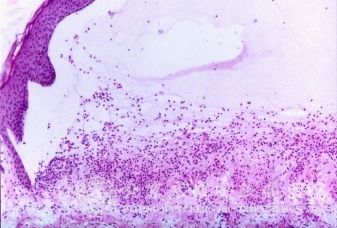

夏季皮炎症状特征有什么?北京京城皮肤医院指出,丹毒是皮肤病中的一种常见的疾病。由于各种丹毒的病因不同,丹毒的症状表都是基本不同的。因此,很多的病人都不是非常了解丹毒到底是一种什么样的疾病。为了帮助广大患者更加了解丹毒,北京京城皮肤医院将为您详细介绍夏季皮炎症状特征有什么。

北京京城皮肤医院指出:皮炎是一种常见的皮肤病,临床上有很多类型,其中季节性皮炎就是之一。

夏季皮炎的病情轻重和气温湿度有密切关系。气温越高、湿度越大,持续天数越长,病情越严重。当天气变凉后,皮肤损害会很快消退而。